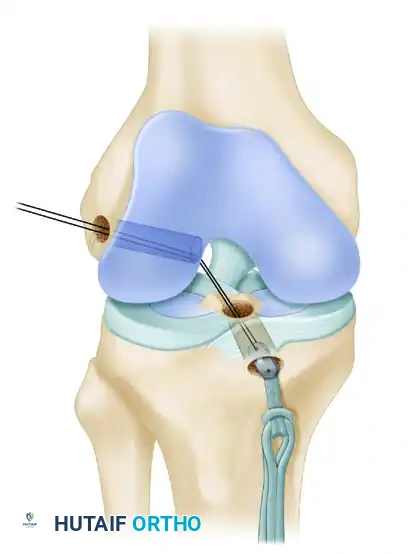

- Guidewire Placement: Leave the femoral guidewire in place. Insert a second guidewire into the anteromedial aspect of the tibia, directing it through the epiphysis using a tibial drill guide.

- Fluoroscopic Verification: From the direct lateral position, externally rotate the C-arm approximately 30 degrees. This specific rotation clearly delineates the physis extending into the tibial tubercle.

- Drilling: Drill the guidewire into the tibial epiphysis under real-time fluoroscopy. You must lift the handle of the drill guide to ensure the wire clears the anterior portion of the tibial physis.

- Joint Entry: The wire should enter the joint at the level of the free edge of the lateral meniscus, precisely within the posterior footprint of the native ACL on the tibia. Arthroscopically confirm the position of both guidewires before proceeding.

- Passage: Place a No. 5 FiberWire passing suture into one end of the EndoButton. Use a suture passer to shuttle this suture from anterior to posterior, up through the tibial tunnel, across the joint, and out through the lateral femoral condyle.

- Femoral Fixation: Pull the EndoButton and tendons up through the tibia and out the femoral hole. Because the transepiphyseal femoral hole is larger than the standard EndoButton, an EndoButton washer (Smith & Nephew, Memphis, TN) that is 3 to 4 mm larger than the femoral hole must be placed over the EndoButton. Apply distal tension to the graft, pulling the EndoButton and washer flush against the lateral femoral condyle cortex.